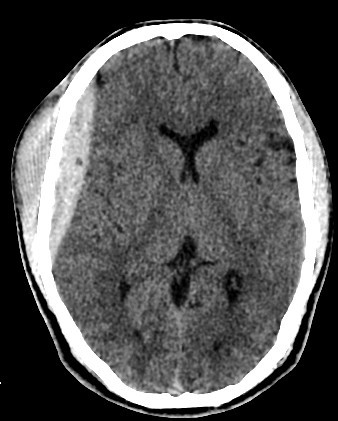

Right Fronto-Parietal

• 30 years old male with trauma

• A well-defined extraxial elliptical shape fresh blood density seen in the right fronto-parietal region.

• The lesion measured ……. cm in its maximal dimensions.

• The lesion exert little mass effect in the form of effacement of the cortical sulci and and mild midline shift.

• right fronto parietal subglial hematoma seen

• associated right fronto parital fracture seen

• no brain herniation.

• Normal size and configuration of the ventricular system.

• No intracerebral or intraventricular recent blood density.

• Normal appearance of the brain stem and cerebellum.

acute extradural hematoma with fracture